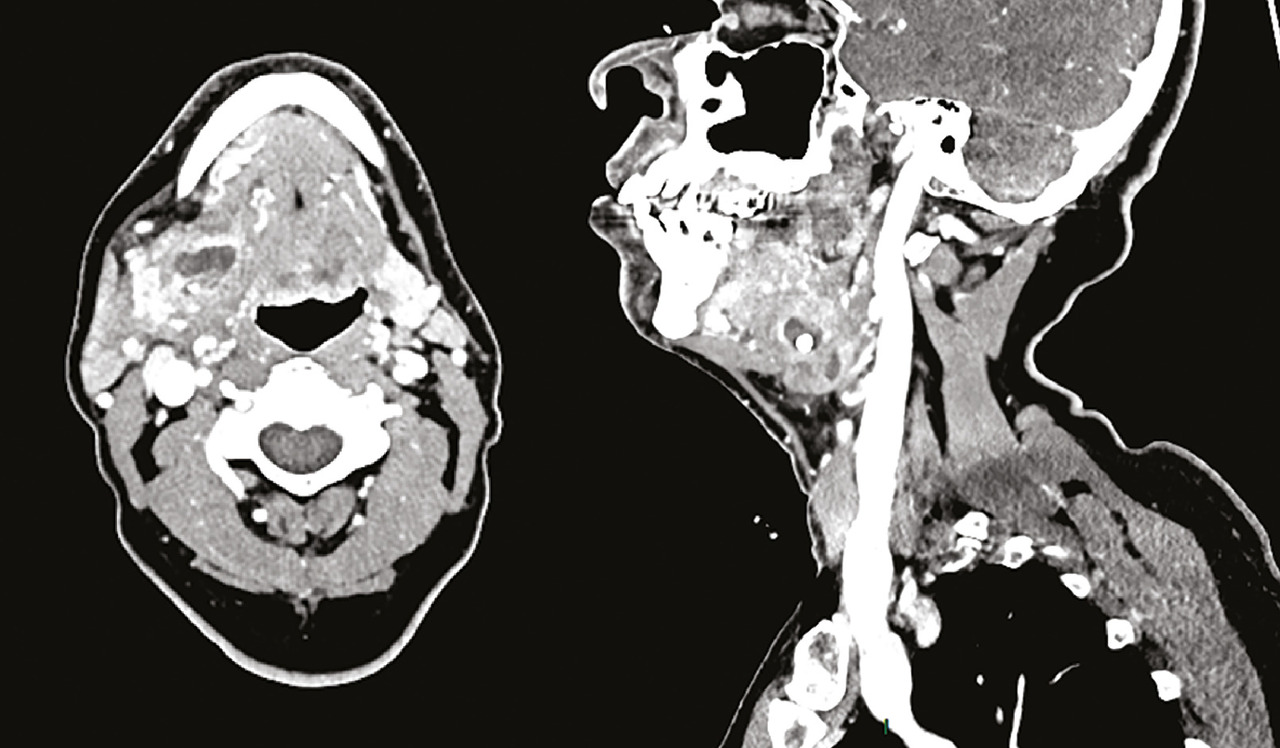

Un examen d’imagerie n’est pas nécessaire en première intention. Cependant, en cas de doute diagnostique, l’échographie est l’examen de première intention : elle montre une glande augmentée de volume, hypoéchogène, avec parfois une dilatation canalaire ou une lithiase visible.6 Elle confirme le diagnostic et recherche des signes de complication comme l’abcès ou la cellulite. Dans ces cas, un scanner avec injection peut orienter vers un traitement chirurgical (Figure ).

En cas d’infection prolongée, récidivante ou en présence de signes cliniques évocateurs de néoplasie, un bilan étiologique par scanner ou échographie est réalisé. Il recherche une pathologie lithiasique ou néoplasique. Le sialoscanner est contre-indiqué à la phase aiguë. L’IRM n’a pas d’intérêt dans un contexte de tableau aigu infectieux.